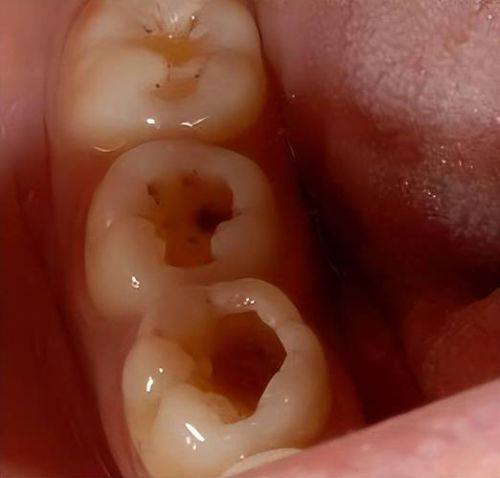

龋洞大小与深度的影响

龋洞的大小和深度是判断是否需要填补的重要因素。如果龋洞比较小而且浅,这时候不用过于着急补牙。我们可以通过改善口腔卫生习惯,比如认真刷牙、使用牙线等,再配合使用含氟牙膏或者氟化物漱口水,促进牙齿的再矿化。牙齿自身有一定的修复能力,在良好的口腔环境下,小而浅的龋洞有可能慢慢修复。

然而,如果龋洞较大或者较深,那就不能掉以轻心了。大而深的龋洞会影响牙齿的结构和功能,牙齿可能会变得脆弱,容易折断。而且,食物残渣更容易残留在龋洞里,滋生细菌,导致龋齿继续发展。所以,这种情况下应该及时填补龋洞,防止龋齿进一步恶化。